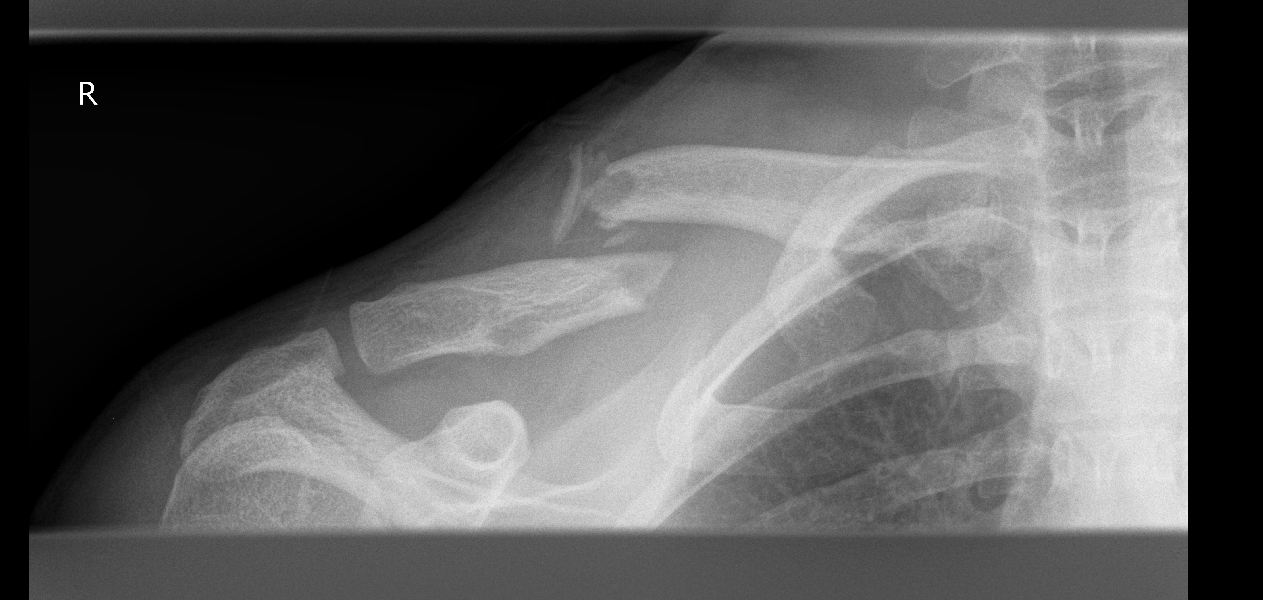

Miniaturansicht angehängter Grafiken

Klicke auf die Grafik für eine größere Ansicht

Name:	kaputt.JPG

Hits:	596

Größe:	80,8 KB

ID:	14990

Naja also bei mir konnte man grob erkennen dass die Enden nicht so ganz richtig liegen ^^

Da kann nichts zusammenwachsen bei der Entfernung

Ich hab im Moment auch n ganz schönen Höcker aufm Schlüsselbein, wenn ich ein Shirt mit etwas weiterem Kragen trage sieht man wie die Ecke da absteht.

Kommt aber im Frühjahr raus die Platte und dann ist auch der Höcker weg.